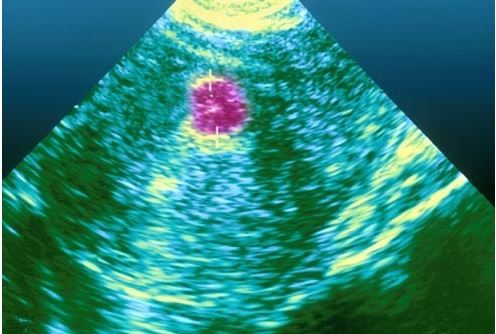

11 常規的骨盆檢查可讓醫生髮現中等或較大的 肌瘤。

超聲波 可顯示 肌瘤 的大小和位置。患子宮肌瘤 想要懷孕的女性

可進行 子宮輸卵管 照影片 來觀測 子宮和輸卵管 情況, 也可防患於未然。